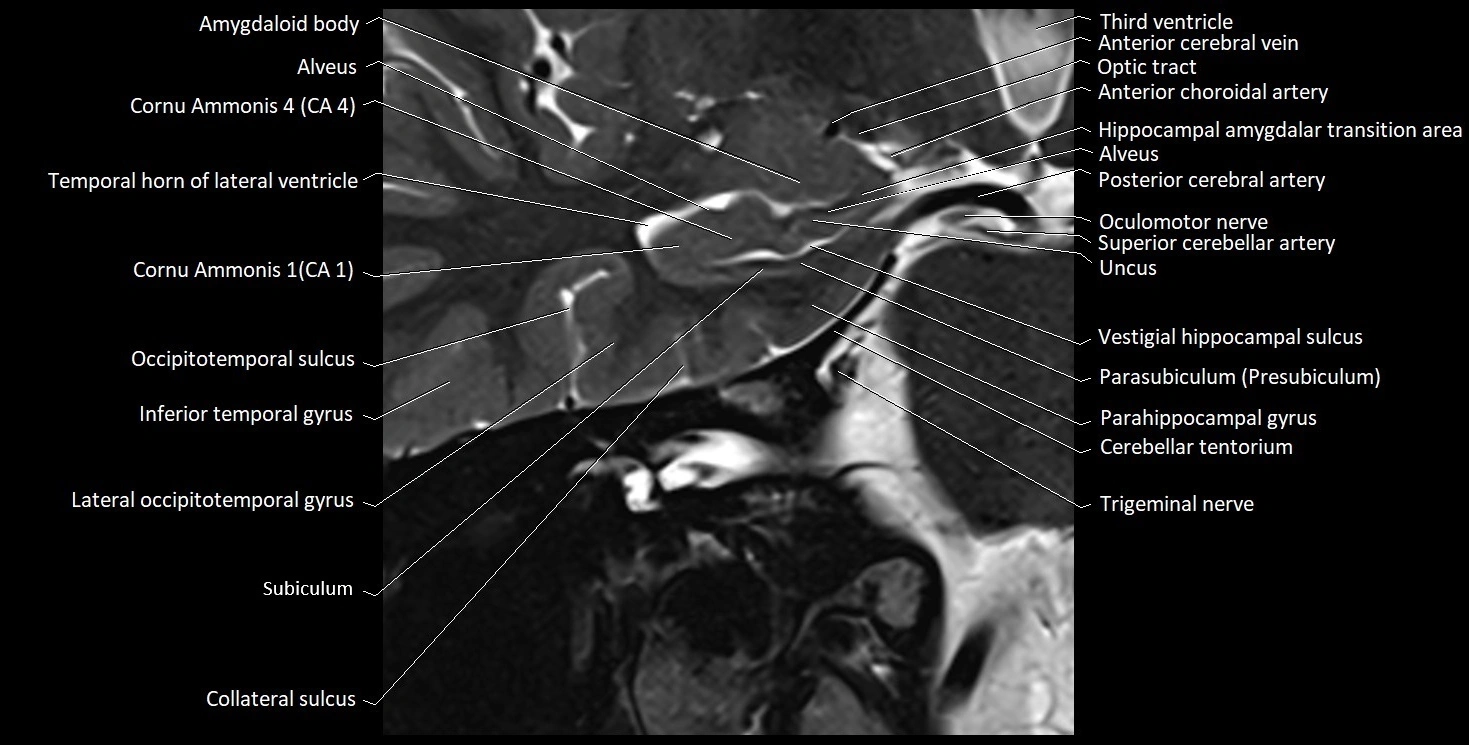

The alveus of the hippocampus is a thin, white matter layer covering the superior (ventricular) surface of the hippocampus within the temporal horn of the lateral ventricle. It consists of myelinated efferent fibers arising primarily from the pyramidal neurons of the hippocampus. These fibers converge medially to form the fimbria of the hippocampus, which continues posteriorly into the fornix, forming a crucial part of the Papez circuit involved in memory consolidation and emotional processing.

The alveus serves as the initial output pathway of the hippocampal formation, linking it to other limbic structures including the hypothalamus, mammillary bodies, and cingulate gyrus. Because of its intimate relationship with the hippocampal head and tail, it is often evaluated in cases of temporal lobe epilepsy, hippocampal sclerosis, and neurodegenerative diseases.

Location and Structure

• Position: Lies on the ventricular (superior) surface of the hippocampus, beneath the ependyma of the inferior horn of the lateral ventricle.

• Composition: A thin sheet of myelinated axons derived mainly from hippocampal pyramidal cells.

• Course: Fibers run medially along the hippocampal surface to form the fimbria of the hippocampus, which curves upward and backward into the fornix.

• Relations:

• Superiorly: Ependyma and CSF of the temporal horn of the lateral ventricle

• Inferiorly: Pyramidal cell layer of the hippocampus (CA1 region)

• Medially: Fimbria and fornix

• Laterally: Temporal lobe white matter and parahippocampal gyrus

Clinical Significance

• Hippocampal sclerosis: Common in temporal lobe epilepsy; the alveus may appear thinned or with altered signal intensity.

• Atrophy: Seen in Alzheimer’s disease and medial temporal lobe atrophy syndromes.

• Tumor invasion: Gliomas or metastases may involve the hippocampal alveus region.

• Surgical relevance: Key landmark in selective amygdalohippocampectomy procedures.

• Imaging relevance: Evaluated in volumetric hippocampal MRI, epilepsy mapping, and neurodegenerative disease imaging.